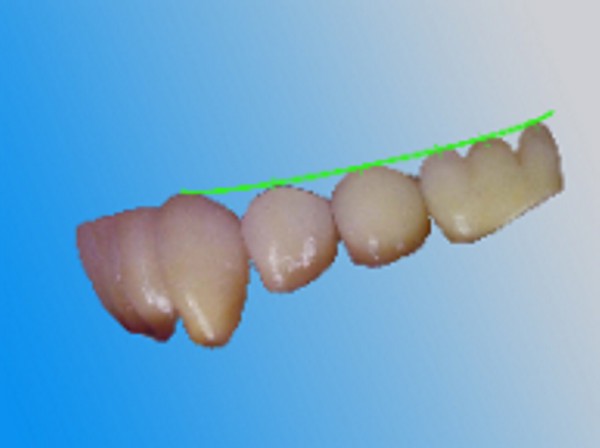

INTRODUCCIÓN El Bruxismo como entidad somática asociada al stress, responde a la mecánica de un Círculo Vicioso Patogénico, que Kawamura describiera hace ya muchos años. FACTOR DESENCADENANTE , que proveen las Interferencias a nivel dentario. En las entregas anteriores se desarrollaron las bases conceptuales de una OCLUSIÓN ORGÁNICA y los efectos de una mayor o menor Desoclusión según la variabilidad de los diferentes Factores Determinantes de la Oclusión. En síntesis; A-La obtención de una Oclusión en Relación Céntrica, nos permite devolver al sistema una elongación muscular fisiológica, sin acortamientos ni estiramientos musculares, sin las consecuentes estimulaciones de los husos neuro musculares, y; una situación estable de la A.T.M. con espacios articulares uniformes. B-El logro de una Guía Anterior que permita desocluir los sectores posteriores durante los movimientos excursivos, nos provée de una segunda y preponderante senda a transitar, que NO estimula por sus contactos excursivos la cincha Pterigo Maseterina, causante de las enormes destrucciones parafuncionales que es frecuente ver en bocas bruxómanas, y la axialización de las fuerzas sobre las piezas posteriores durante el cierre. C-Otorgando como consecuencia, Estabilidad a la tabla premolar-molar, simultaneidad en la recepción de fuerzas durante el cierre(A.T.M. y superficies oclusales). Obtendremos así una Oclusión estable y fisiológica, que no genere el FACTOR DESENCADENANTE del Bruxismo, siempre presente a nivel dentario. INTRODUCTION Bruxism as a somatic entity associated with stress responds to the mechanics of a Pathogenic Vicious Circle, described by Kawamura many years ago. Summarsing: A-Obtaining an oclusion in a Central Relation, allows us to return to the sistem a physiological muscular elongation, without muscular shotthenings or lenghthenings, without the following stimulations of the neuro-muscular huses and a stable situation of the Temporo Mandibular Joint with uniform articular spaces. B-The accomplishment of an Anterior Wide wich may allow disclusive the posterior sectors during the excursives movements, and the axial forces during the mandibular closure. C-Providing as a consecuence, axiality and stability to the posterior sections, responsible of the mandibular closure, through Sttopers, Equalitzers, A, B and C, to obtain a Oclusión Mutuamente Compartida: forces reception during mandibular closure (T.M.J. and Oclusal Surfaces) By this procedure, we should obtain a stable and physiological oclusion, that will not generate the chain link of factors that lead to Bruxism, always present at the dental level. MATERIALES Y MÉTODOS: La funciones articular y muscular, se analizaron mediante Bio Pack, en el pre, en el intra y en el post operatorio. Durante el diagnóstico, tratamiento y remontas, se utilizaron articuladores semi ajustables Wip Mix, totalmente ajustables Artex y arcos faciales correspondientes. El encerado de dianóstico se realizó, mediante la técnica de encerado progresivo de Peter K. Thomas. Los refuerzos a Perno Colado se llevaron a cabo con oro BIODENT YELLOW de ARGEDEN. Los tres juegos de provisionales utilizados, se hicieron con metacrilato termo curado. Las Restauraciones Periféricas Totales, fueron realizadas mediante porcelana CREATION de WILLY GUÉLLER, sobre oro BIODEN YELLOW de ARGEDEN. Los chequeos de los Contactos Interoclusales, se midieron con papeles de articular de 40 y 12 micrones, y mediante el analizador computarizado T-Scan. DESARROLLO Paciente varón de raza blanca, 42 años, complexión robusta y marcada hipertrofia maseterina. Fig.1 Fig.2 Fig.5 Se realiza un análisis pre-operatorio articular y muscular mediante Bio Pack, y oclusal mediante T-Scan, cuyos resultados muestran una evidente hiperactividad muscular en Temporal Anterior y Masetero Derechos, y contactos totalmente anómalos tanto en Oclusión Habitual como en Excéntricas. Fig. 6-7-8-9-10-11 Sensor de ruidos articulares Luego del primer intento de relajación mediante Laminillas de Long (Ref.6),Fig.12, registros y montaje, se observa la aparente presencia de una relación Borde a Borde, que luego se comprobaría que se trataba de una propulsión exagerada de su mandíbula en la búsqueda de contactos efectivos. Fig. 13-14 (Obsérvese el fenómeno de Patterson dado por la exclusiva guía de movimiento de la A.T.M. y la carencia de la Guía Anterior) Se procede a construir un JIG de LUCIA para lograr una desprogramación muscular adecuada, y se le indica permanecer con el colocado durante toda la noche anterior a la consulta, sin contactos dentarios posteriores. Aún en la duda, de que la obtenida sea una posición articular fisiológica, se procede a construir una Placa de Relajación sobre el último montaje obtenido, la que se ajusta cada dos días, y al cabo de tres semanas se procede a un tercer montaje obtenido de la nueva situación posicional. Fig.17-18 Se verifica entonces que estamos en realidad, ante una presunta CLASE II, después de tres métodos diferentes de relajación y transcurridos más de un més de múltiples sesiones para lograr una posición diagnóstica confiable a partir de donde comenzar a trabajar.(O.R.C.) Se adicionan entonces topes (montículos) en las caras oclusales de los primeros molares de la Placa de relajación, transformándola en una Férula Pivotante, de levísima altura, impidiendo el contacto de las demás piezas dentarias a fin de convertir la palanca en una de clase II (fisiológicamente el sistema se mueve según una palanca de clase III), y obtener de esa forma una descompresión de los espacios articulares, ya que si bien la A.T.M. era asintomática, estaba muy claro que la Dimensión Vertical Posterior se presentaba disminuida debido al exagerado desgaste de todos los sectores posteriores, cuya típica forma de «desgaste en olla», se verificaba en el análisis estático de los modelos.( Ref.7) En esa situación se remonta el modelo inferior puesto que el superior no modifica su posición espacial, y se realiza un Encerado de Progresivo Diagnóstico según PKT, previo análisis de los modelos mediante los analizadores de W.McHorris (Ref.8) Fig.18-19-20-21-22-23-24-25-26-27-28-29-30 Fig.18 Fig.22 Fig.23 (Obsérvese, que la Disclusión Propulsiva comienza en los rebordes mesiales del canino, sigue en los rebordes distales del lateral, y finaliza con los rebordes mesiales de los centrales.) Se realizan las endodoncias de toda la boca y se tallan los endodontos para la construcción de Pernos Muñones Colados de oro, los que se realizarán mediante técnica indirecta sobre los modelos :montados según los logros de todos los procedimientos de relajación. Se torna imprescindible la extracción de tres piezas dentarias, para la confección de la Guía Anterior, cuyo alineamiento hubiera sido imposible mediante técnicas reconstructivas ya que la posibilidad ortodóntica no era viable dadas las condiciones de desgaste. Fig.31-32-33-34-35-36-37 (Obsérvese, que desde la configuración de los Pernos Muñones Colados, se determina ya la Alineación Tridimensional que otorgaremos a la Rehabilitación Oral Integral del caso. Se monta entonces el primer juego de Provisionales de acrílico de termo curado, obtenido de la réplica del Encerado de Diagnóstico. Fig.38-39-40-41 (Obsérvese la presencia del ajuste periférico y las disclusiones, tan importantes en las provisorias como en las definitivas ya que del resultado de la etapa de provisionales, dependerá el éxito final.) Se ajustan las Unidades de Oclusión mediante Ajuste Oclusal (según técnica propuesta por la Cátedra de Operatoria Dental II y Prótesis de la Fac. de Odontología, Univ. Bs. As., Prof.Anibal Alonso.) Se deja actuando la nueva situación durante seis meses. Han transcurrido seis meses durante los cuales se instaló un nuevo juego de provisorios con las mismas características del anterior, y clinicamente no se observa hiperactividad muscular, perforaciones de los provisorios, molestias para desmenuzar los alimentos ni síntomas alguno en la A.T.M. NOS ENCONTRAMOS, CON UN SISTEMA EN PAZ A TODOS SUS NIVELES. Se procede entonces a la toma de impresiones definitivas, mediante la técnica de Impresión a Presión Masticatoria, para la confección de las restauraciones permanentes, y los metales se chequean mediante llaves de Duralay, para observar la situación análoga entre laboratorio y clínica.(Corroboración de la Oclusión en Relación Céntrica)Fig.42-43-44 Se prueban los metales y verifica su ajuste periférico. (Obsérvese que también en los metales sub porcelana se siguen las formas de las Preparaciones Funcionales, permitiendo de esta manera un perfecto bizcochado de la porcelana supra metal.) Realizada la Guía Anterior, Determinante Oclusal Primario y Anterior en el laboratorio, se prueban en boca sus características estáticas: Altura Funcional, Ángulo de la Disclusión y Punto de Acoplamiento, como así las dinámicas: Laterotrusión Derecha e Izquierda y Propulsión. En este estado las cosas, tenemos al sistema circunscripto tanto estática, como dinámicamente, por el gobierno de dos comandos, ya en Oclusión en Relación Céntrica, como en las Transtrusiones: Sabemos que todo lo que construyamos (tabla premolar-molar), entre estos dos comandos rectores del movimiento, partirán del mismo punto y volverán a el, transitando el recorrido impuesto por los mismos. Se construyen entonces en el laboratorio, las unidades de oclusión de premolares y molares, siendo las correspondientes a los cuatro últimos molares, con oclusal en oro, como un elemento de detención del cierre más poderoso que la porcelana.47-48-49-50-51 Se prueban en boca la Curva de Wilson, la Curva de Spee, la Alineación Tridimensional, los Espacios Uniformes Disclusivos, la Dirección de los Surcos de T, nT, y P, y los Puntos Interoclusales de Contacto. En laboratorio se retocan entonces los Puntos Interoclusales de contacto, acercando los mismo a la mejor posición ideal lograble, y luego de una nueva prueba en boca, se glacéan las piezas y se instalan en forma provisional durante 24 hs. Verificada la eficacia de las formas (FORMA=FUNCIÓN), se procede a constatar la eficiencia de la dinámica trayectorial y se cementan con cemento de fosfato mediante la técnica de cementado alterno. Fig.54-55-56-57-58-59-60-61-62-63-64-65-66-67-68-69. Fig.54 Fig.55 Curva de Wilson y Alineación Tridimensional en molares y premolares sup. Der. Fig.56 Fig.57 idem inferiores derechos Fig.58 Fig.59 Idem superiores izquierdos CONTACTOS INTEROCLUSALES SUPERIORES CONTACTOS INTEROCLUSALES INFERIORES Transcurrido un mes de instalada la Rehabilitación, se lleva a cabo un nuevo estudio, post operatorio con Bio Pack y Tscan. CONCLUSIONES : I-El paciente realiza una apertura bucal de 45mm sin forzamientos siguiendo una misma línea de apertura sin desvíos. II-Las disclusiones en laterotrusión se llevan a cabo mediante un recorrido lineal sobre los rebordes medios de ambos caninos superiores, creando un fenómeno de Luce con espacios uniformes en ambos lados. III-La disclusión en propulsión se manifiesta comenzando en los rebordes mesiales de ambos caninos, siguiendo por los rebordes distales de laterales y terminando en los rebordes mesiales de ambos centrales, dando lugar a un fenómeno de Christensen con espacios uniformes de ambos lados. IV-Los contactos interoclusales son suficientes, simultáneos y tripódicos logrando la estabilidad en ambos planos del espacio tanto de las piezas individuales como en conjunto, sin contactos deflectivos. V-Realizado un nuevo montaje de la boca terminada, corroboramos como estable la Oclusión en Relación Céntrica. VI-No existen movilidades dentarias y los tejidos periodontales y gingivales se encuentran estabilizados. VII-No existen ruidos articulares. VIII-El resultado post operatorio Bio Pack de la dinámica mandibular, muestra una sustancial mejora de los movimientos en los tres planos del espacio. IX-Electromiográficamente, se observan contracciones musculares dentro de los rangos de normalidad, persistiendo un rango ligeramente elevado en temporal anterior y masetero del lado derecho, presumiblemente debido a la hipertrofia que dicho paciente traía, y mostraba en el estudio pre-operatorio. COMPARACIONES PRE, INTRA Y POST OPERATORIAS Sonografía de la ATM: Tanto en el examen pre como post operatorio no se observaron ruidos de ningún tipo, coincidiendo con la exploración clínica pre auricular e intra auricular. Electromiografía: La electromiografía en reposo, muestra bien a las claras la presencia de músculos hipertónicos durante el estudio pre operatorio, fundamentalmente del grupo Temporal Anterior y Digástricos, estando el Masetero izquierdo ligeramente por encima de su rango normal como así también ambos Esternocleidomastoideos. Durante el estudio post operatorio, se verifica el estado tónico de todos los grupos musculares, persistiendo una ligera hipertonicidad de rango levemente por encima de lo fisiológico, en el Temporal Anterior Derecho y Digástrico Derecho. PRE OPERATORIO POST OPERATORIO Temporal Ant. Der. 4.4 2.8 Temporal Ant. Izq. 6.2 1.1 Masetero Der. 1.2 0.5 Masetero Izq. 1.5 0.8 Est.Cleid.Mast. Der. 1.6 0.3 Est.Cleid.Mast. Izq. 2.1 0.2 Digástrico Der. 1.7 2.9 Digástrico Izq. 1.6 0.7 (La unidad de medida utilizada es el microvoltio ) Dinámica mandibular: Durante el Pre Operatorio, en el Plano Sagital, tanto la Apertura como el Cierre lento, se manifiesta mediante una acentuada tendencia a propulsar la mandibula. Durante el Post Operatorio, la tendencia hacia la derecha de estos dos últimos planos se mantiene, mientras que en Plano Sagital, la propulsión inicial no se produce, asemejándose el movimiento a la primera fase del Bicuspóide de Posselt. El Análisis de la Dinámica realizado durante la Masticación (chicle), nos muestra en el Plano Sagital, la propulsión mencionada durante la apertura y cierre lentos durante el estudio Pre Operatorio, se aproxima a la normalidad durante el Intra Operatorio (2º juego de provisionales), y se vuelve a manifestar propulsivo, en el Post Operatorio. En cuanto al Plano Frontal, durante el Pre Op. , ofrece un Ciclo Masticatorio(recordar la forma de «gota de agua») para el lado izq., con componentes derechos e izquierdos alternos, que se aproximan paulatinamente al Ciclo Masticatorio Normal, durante el Intra y Post Operatorio. El Plano horizontal, confirma las afirmaciones anteriores durante los tres períodos de estudio. ANÁLISIS MEDIANTE TSCAN 1-Bio Pack Bio Research Associates,Inc Distrib.UEDA S.A. 2-Wip Mix-Artex 3-Au:89% / Pt:6% /Elementos complementarios:5% 4-Idem ref.3 5-Tscan TekSkan,Inc Distrib.UEDA S.A. 6-Mc Horris.Cátedra de Operatoria Dental II y Prótesis. 7-Alonso.Cátedra de Operatoria Dental II y prótesis. 8-Mc.Horris. Analizadores de Guía Anterior. BIBLIOGRAFÍA: 1-Esquemas de las dos primeras entregas, tomadas del libro:»Oclusión Orgánica…un camino hacia la Rehabilitación Oral» 2-Oclusión y Diagnóstico en Rehabilitación Oral. 3-Anatomia Odontológica. 4-A contribution to the study of the movementes of the mandible. 5-Celenza F.W, Nadeskin J.F.,Oclusión.Situación actual. 6-D´Amico 7-Dawson P.E. 8-Huffman -Regenos. 9-Hobo S.-Takayama H.A. 10-Lucia V.O 11-Mc Horris. 12-Mc Horris. 13-Posselt U. 14-Stuart C. 15-Vartan Veshnilian AGRADECIMIENTOS: La Rehabilitación Oral, especialidad donde se hace imprescindible el manejo y concurrencia de todas las especialidades dentales en su desarrollo más depurado, no tendría razón de ser, sin la más estrecha colaboración de una técnica para- médica con detalles de excelencia. Sr. Pedro Colomina: muchas gracias. Pedro Colomina. – Titulado especialista en prótesis dental en la escuela Ramon y Cajal de Barcelona 1988

Al cabo de los mismos se realiza una nueva comprobación del estado articular y muscular mediante Bio Pack y un chequeo oclusal mediante T-Scan, donde se observan una evidente mejoría de la musculatura comprometida, de la dinámica mandibular, de la apertura bucal, de los contactos simultáneos de la Oclusión en Relación Céntrica como así de las Excéntricas, y un manifiesto control masticatorio por parte del paciente.

Durante esta última, se obtiene un comienzo en los rebordes mesiales caninos, luego los laterales y por último los centrales, tal como se concibió en el encerado.

También se observan las características estéticas logradas.

Se confirma nuevamente la centricidad mandibular a través del contacto canino simultaneo, y se toma con la G.A. instalada (comando anterior de la desoclusión), un nuevo registro intermaxilar. Fig.45-46

Guía Anterior sobre Rebordes Palatinos Superiores